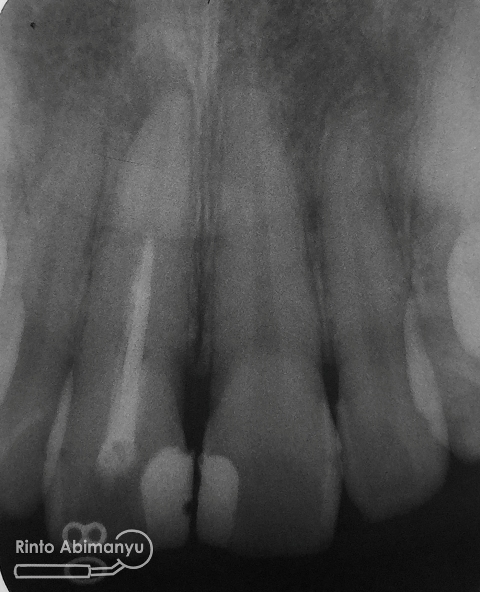

Ternyata dari foto ronsen diketahui gigi 11 pernah dilakukan perawatan saluran akar tetapi pengisiannya tidak sepanjang kerja..

Ini ronsennya…

Foto radiografis awal gigi 11